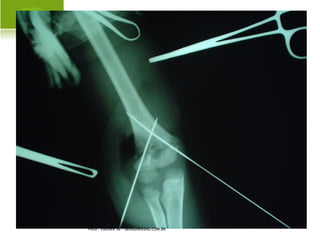

F RATURA - LUXAÇÃO OMBRO

PROF. VAGNER SÁ - SAVAGNER@IG.COM.BR

L ESÃO NERVOSA ASSOCIADA